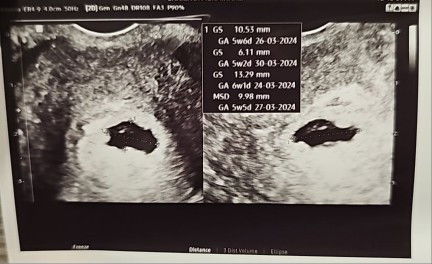

I went to see gynae yest for first time at 5W5D, she told me that my sac is irregular in shape. She told me to come again nx wk to check again for the sac as its still in the early stages. I know this is not really a good news. I told my husband to accompany me for the appointment nx wk. Anyone experienced smth similar before? Open to any advice and help. Thanks #advicepls #pleasehelp #FTM #firstbaby #firsttimemom #firstmom #irregulargestationalsac